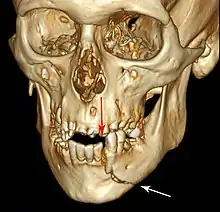

| 3D computed tomographic image of a mandible fracture in two places. One is a displaced right angle fracture and the other is a left parasymphyseal fracture. | |

3D CT reconstruction of mandible fracture, white arrow marks fracture, red arrow marks moderate displacement and open bite